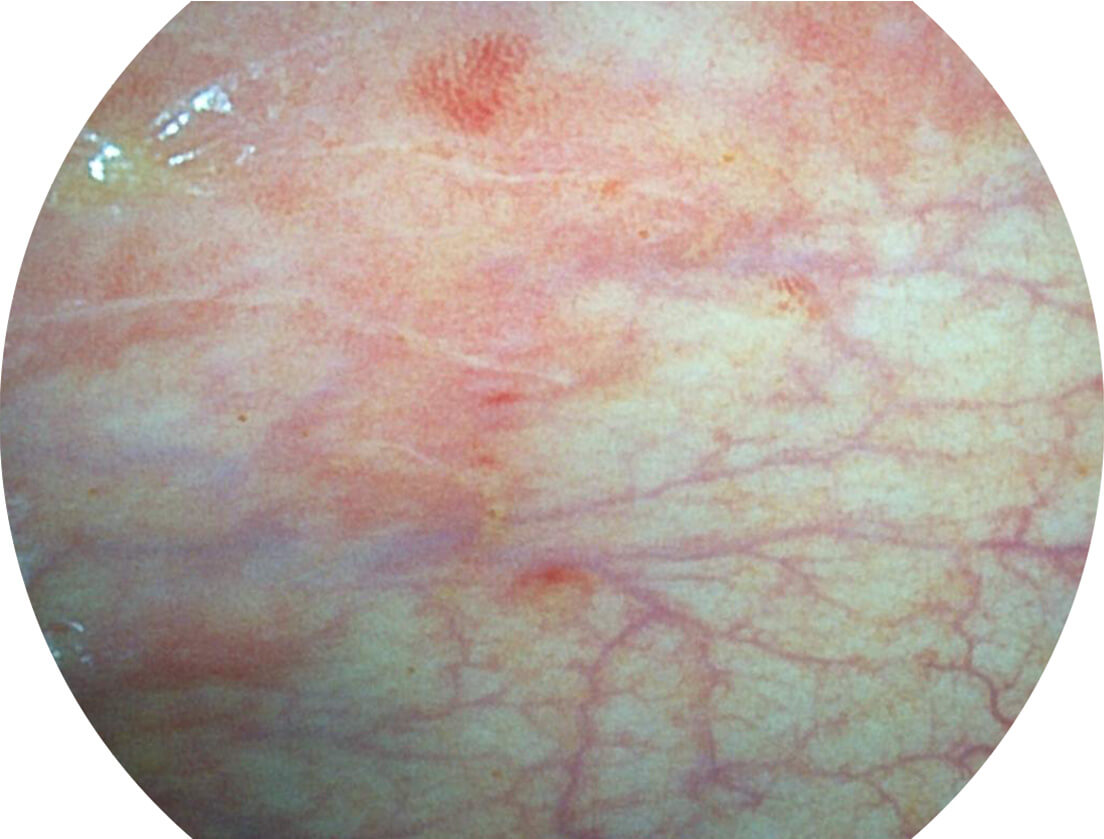

Spectral Focused lmaging, SFI

图像具有高亮度、高黏膜血管颜色对比度的特点,且不改变粘液、食物残渣、粪便的基本颜色,可在中远景下进行观察,助力消化道早期疾病的诊断。

白光图像

白光图像

SFI图像

SFI图像

白光图像

白光图像

SFI图像

SFI图像

白光图像

白光图像

SFI图像

SFI图像